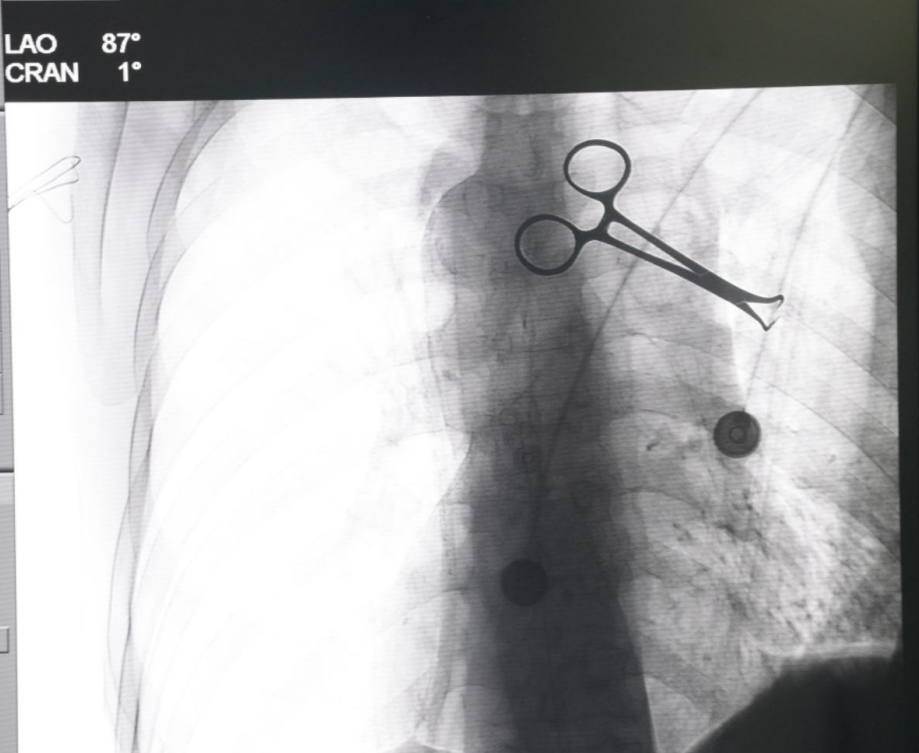

在手术室、麻醉科的密切配合下,手术顺利进行,李思锦主任带领疼痛科韩春莹医生、王金明医生凭借精湛的技术和丰富的经验,将鞘内药物输注系统精准地植入患者体内。不仅大幅减轻患者疼痛,还显著降低阿片类药物带来的诸如恶心、呕吐、便秘等副作用。患者及其家属对此次治疗效果表示非常满意。